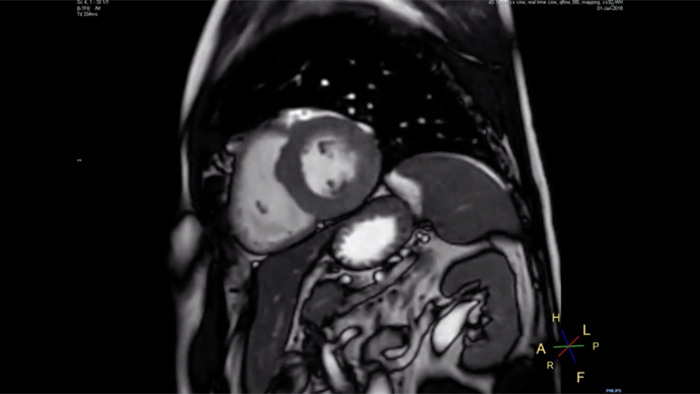

Philips Compressed SENSE reduces the time spent in the MRI scanner for the patient. Furthermore, Compressed SENSE enables the reduction of breath hold times which has the potential to improve compliance with an MRI scan.

4.8 sec breath hold time

Since short breath hold times make it easier for our patients to comply, the failure of breath holding largely disappeared.

At our facility, we found in Cardiac MR fewer breath holds are now needed, or breath hold times are shortened."

Dr. Takashi Koyama, MD, PhD, Diagnostic Radiologist and Director of the Department of Radiology Center and Diagnostic Radiology, Kurashiki Central Hospital, Japan

A 15- or 16-second breath-hold is tough for many cardiac patients. With Compressed SENSE we actually have protocols now that can get that below 10 seconds. It’s a lot easier to get through for a patient, and patients are a lot more satisfied with the experience.”

Trevor Andrews, Ph.D., MR Physicist, University of Vermont Medical Center, USA